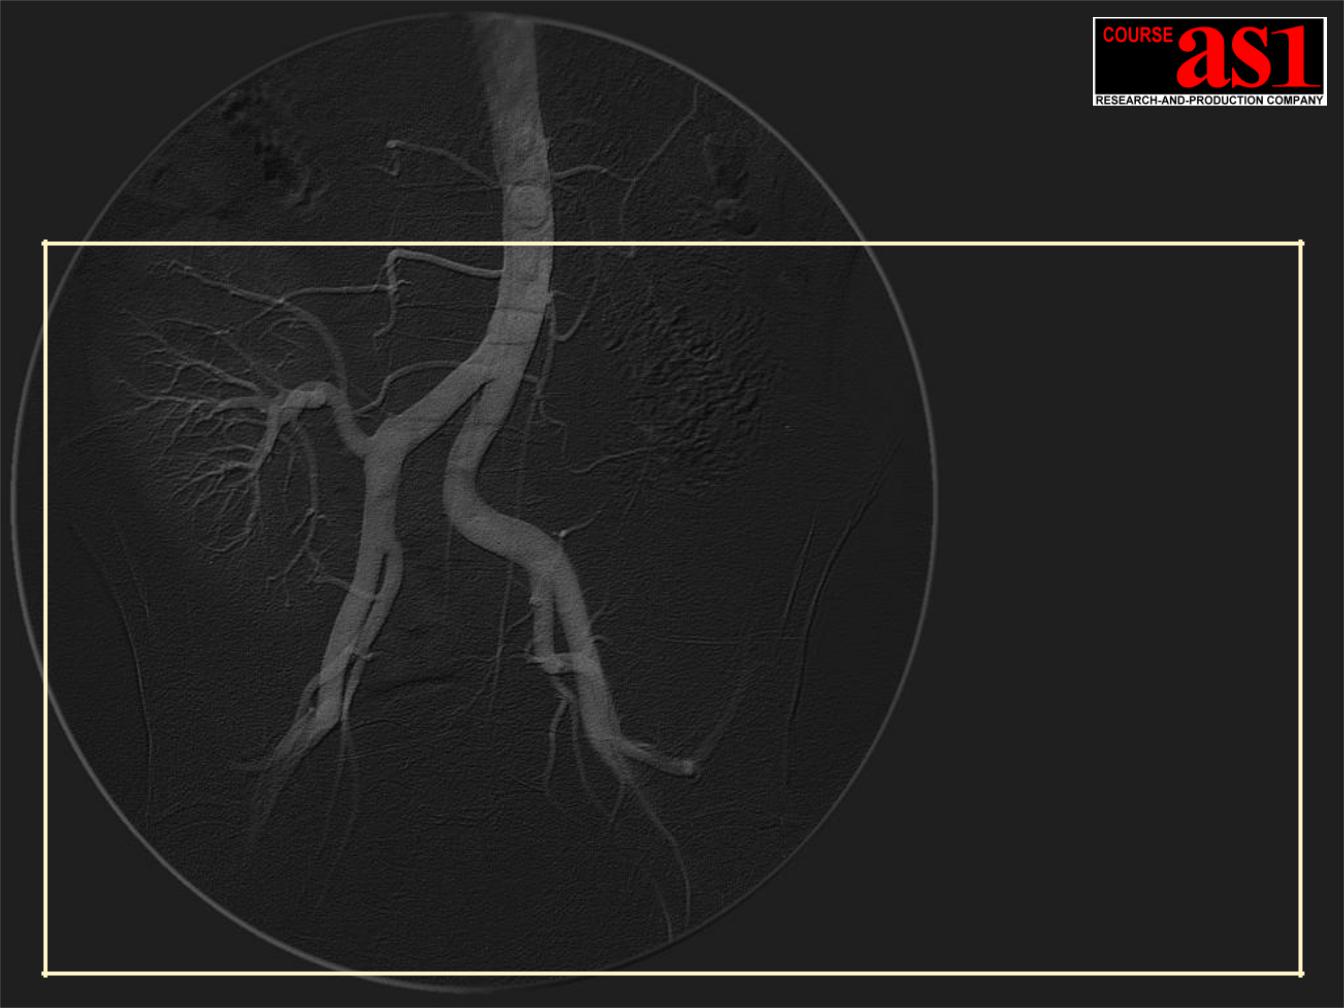

4. Режим Субтракционной Ангиографии Реального Времени – Subtraction Angiography (DSA) сверхвысокого разрешения 9Mpix/30fps или 2Mpix/60fps.

5. Режим Ротационной Ангиографии Rotational Angiography (RA) сверхвысокого разрешения 9Mpix at 30fps, включая DSA режим.